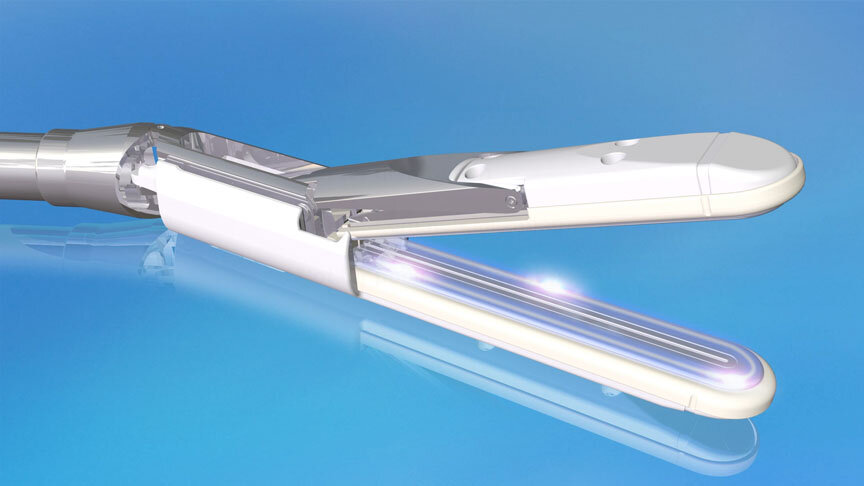

Erectile Dysfunction

Medtronic Corporation

This animationis intended to explain Erectile Dysfunction to physicians. It shows the vessels and nerves involved in blood flow obstruction to the penis, and the erectile tissue's failure to enlarge. The animation also suggests the benefits of clearing the obstruction by using stents.